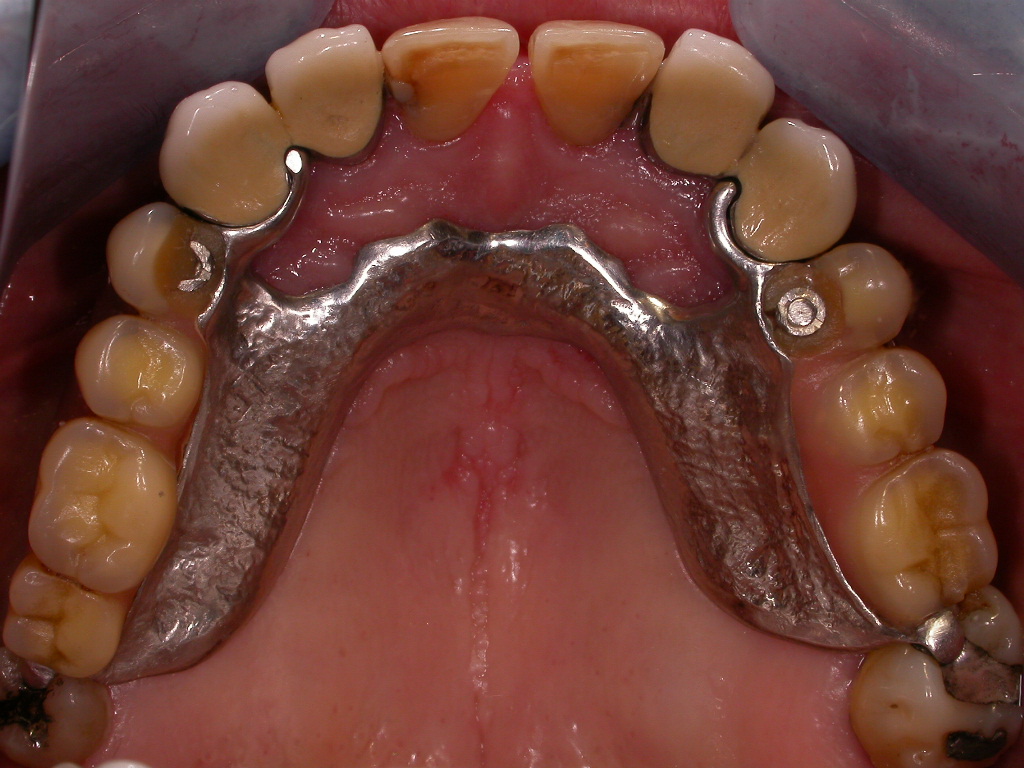

Herausnehmbare Modellguß-Prothese

Vorher: Herausnehmbare Modellguß-Prothese

Feste Zähne mit 8 Implantaten; aus Kostengründen wurden zwei alte Kronen mit dem Goldrand belassen

Nachher: Feste Zähne mit 8 Implantaten; aus Kostengründen wurden zwei alte Kronen mit dem Goldrand belassen